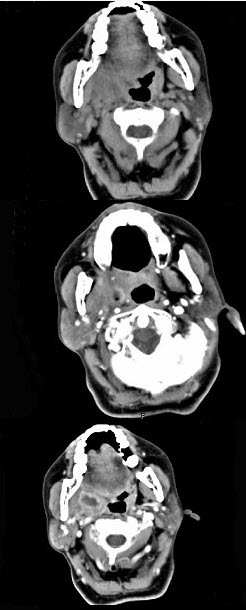

女,52岁,咽喉部疼痛半个月,伴低热,CT如图所示,可能诊断为()。

A、咽旁脓肿

B、咽部神经鞘瘤

C、鼻咽血管纤维瘤

D、咽旁淋巴瘤

E、咽旁转移癌

正确答案:

A